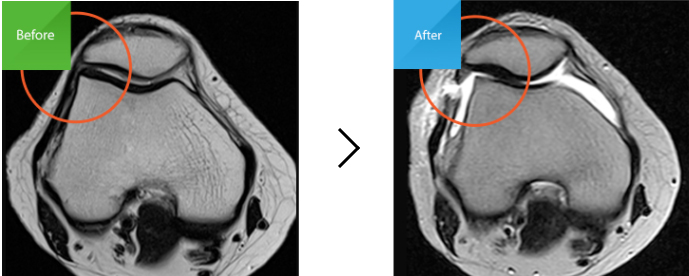

외측지지대가 좁아져 있는 상태(MRI)

외측지지대를 터서 벌어진 상태(MRI)